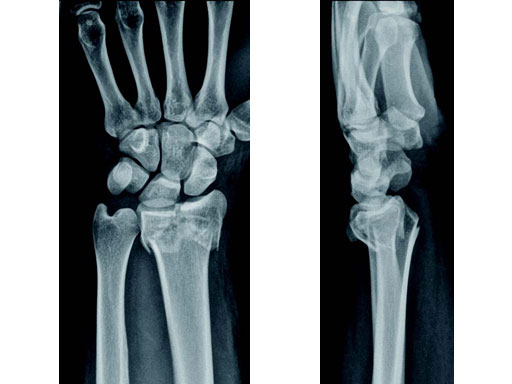

Case 1: 22-year-old male fell off a horse while playing polo.

Case provided by Ladislav Nagy, Zrich, CH

Fig 1a-b Preoperative x-rays.